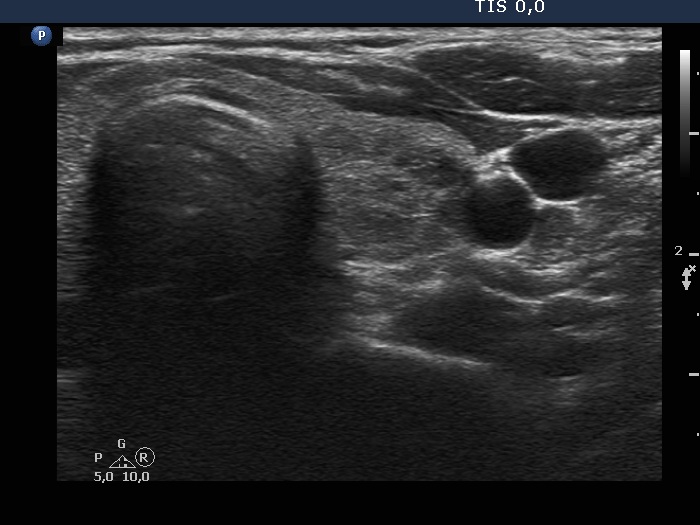

Lower third of the left lobe, another transverse scan.